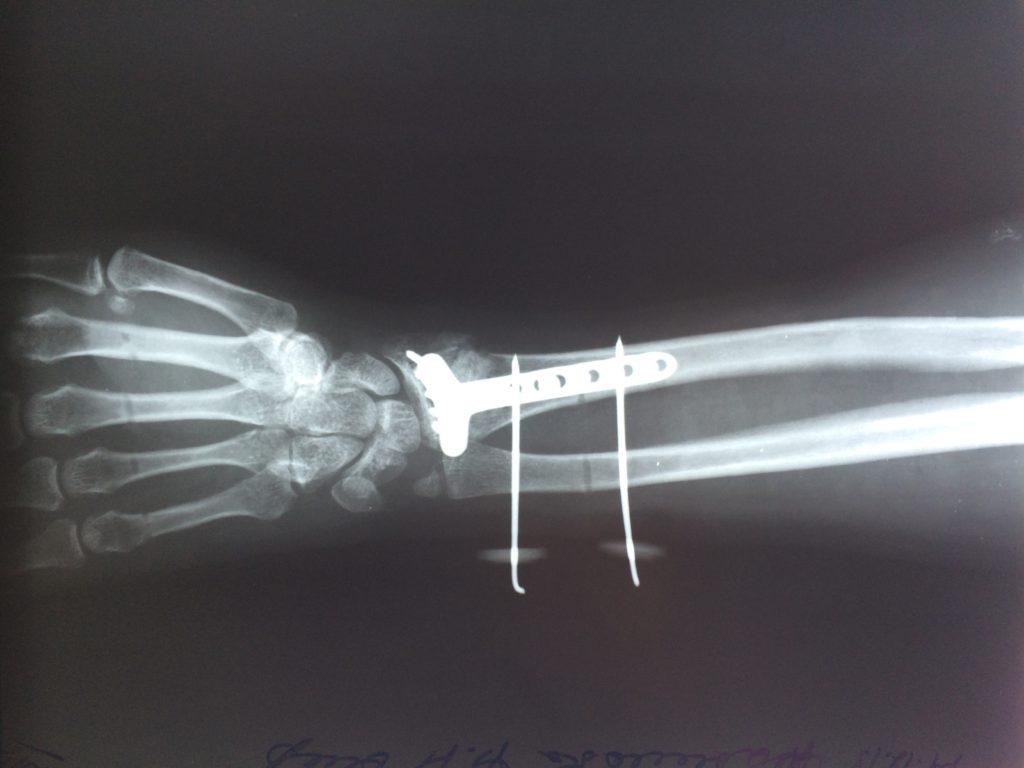

Операция - открытая репозиция, остеосинтез лучевой кости пластиной с костной ксенопластикой материалом "Остеоматрикс". На контрольных снимках в три месяца имеется консолидация перелома, миграции фиксатора нет, имеется остеоинтеграция ксенопластического материала.

Отдаленные результаты через 6 (шесть) месяцев